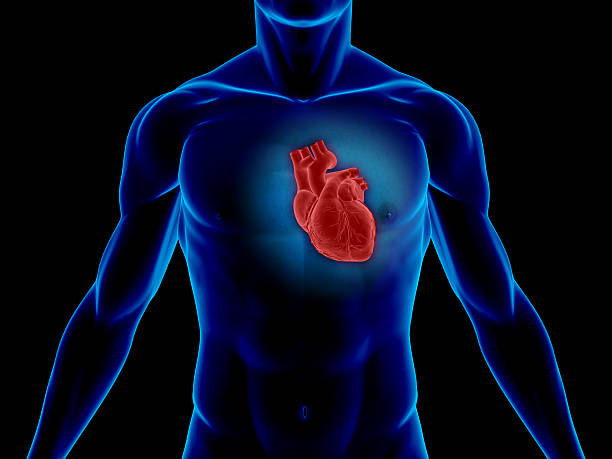

They are structural abnormalities of the heart, usually related to an abnormal or incomplete formation of cardiac structures. Sometimes they are related to hereditary factors, and sometimes they are caused by environmental alterations or medications, although the great majority have unknown causes (there are isolated mutations).

They have a high anatomical variability. We have to imagine the heart as a puzzle in which the different structures (veins, atria, ventricles, vessels, etc.) can take any position and any defect can exist (absence of septa, single vessel, single ventricle, etc).

Its importance lies in the physiopathological focus (what it produces in the child). Therefore, it is necessary to know its anatomy and what it causes: a mixture of desaturated blood (not carrying oxygen) that will give the child a blue colouration (cyanosis) or an increase in the amount of blood going to the lungs, causing more blood to return to the heart and generate “fatigue” (heart failure, which in young children manifests as a lack of growth, difficulty gaining weight and fundamental breathing difficulties).

In the following link you can access an external website to get more information on how to understand a normal heart and blood circulation.